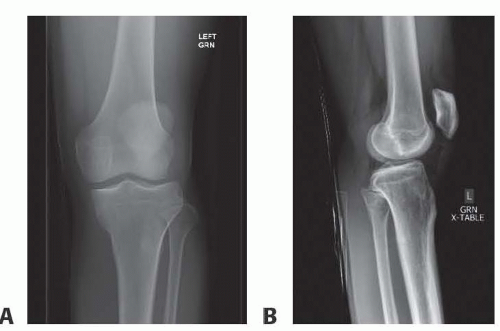

IMAGING